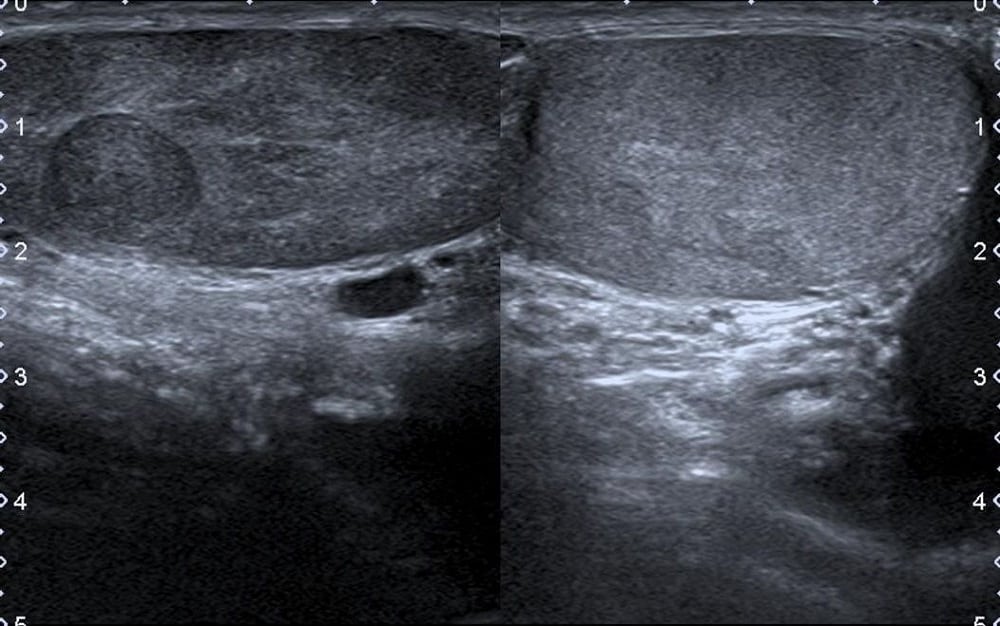

टेस्टिकुलर अल्ट्रासाउंड अंडकोष से संबंधित परिक्षण है। जिसका मुख्य उद्देश्य अंडकोष यानि कि टेस्टिकल (Testicles) संबंधित समस्याओं की जांच करना है। इसमें उच्च-आवृत्ति ध्वनि तरंगों (high-frequency sound waves) के जरिए अंडकोष और आसपास के ऊतकों की तस्वीरें निकाली जाती है। जिससे अंडकोष, अंडकोष की थैली (scrotum) और उसमें उपस्थित नसों की विस्तृत तस्वीर ली जाती है। इस टेस्ट को डॉक्टर्स स्क्रॉटल अल्ट्रासाउंड भी कहते हैं।

टेस्टिकुलर अल्ट्रासाउंड को विभिन्न तरह की समस्याओं की जांच के करने को कहा जाता है, जैसे- वृषण में मरोड़ (testicular torsion), अंडकोष में कैंसर और एपिडिडिमिटीस । डॉक्टर तब भी टेस्टिकुलर अल्ट्रासाउंड कराने के लिए कहते हैं जब आपके अंडकोष के थैले में सूजन और दर्द होता है। ऐसे में टेस्टिकुलर अल्ट्रासाउंड कैंसर की समस्या को बताने में मदद करता है। इससे सिस्ट या ट्यूमर के बारे में पता लगाया जा सकता है। इस टेस्ट से ये पता लगाया जा सकता है कि स्क्रॉटम में खून का प्रवाह सही से हो रहा है या नहीं।

टेस्टिकुलर अल्ट्रासाउंड को करने में लगभग 30 से 45 मिनट का समय लगता है। अल्ट्रासाउंड की प्रक्रिया के दौरान ऑपरेटर आपको एक करवट लेटा देंगे। इसके बाद अल्ट्रासाउंड की प्रक्रिया शुरू करते हैं। अल्ट्रासाउंड हाथों से संचालित करने वाली एक छोटी सी मशीन, जिसे ट्रांसड्यूसर कहते हैं और ये ही तस्वीरें निकालता है। डॉक्टर वॉटर-बेस्ड जेल को स्क्रॉटम यानी की अंडकोष पर लगाते हैं। ऐसा करने से त्वचा और ट्रांसड्यूसर के बीच अच्छा संपर्क बन सके और तस्वीरें साफ-साफ आ सके। इसके बाद ऑपरेटर स्क्रॉटम पर ट्रांसड्यूसर को घुमाते हैं। जिससे पास में रखे मॉनिटर पर तस्वीरें आने लगती हैं। परीक्षण पूरी तरह होने के बाद ऑपरेटर स्क्रॉटम पर लगाए हुए जेल को पोछ कर साफ कर देते हैं।